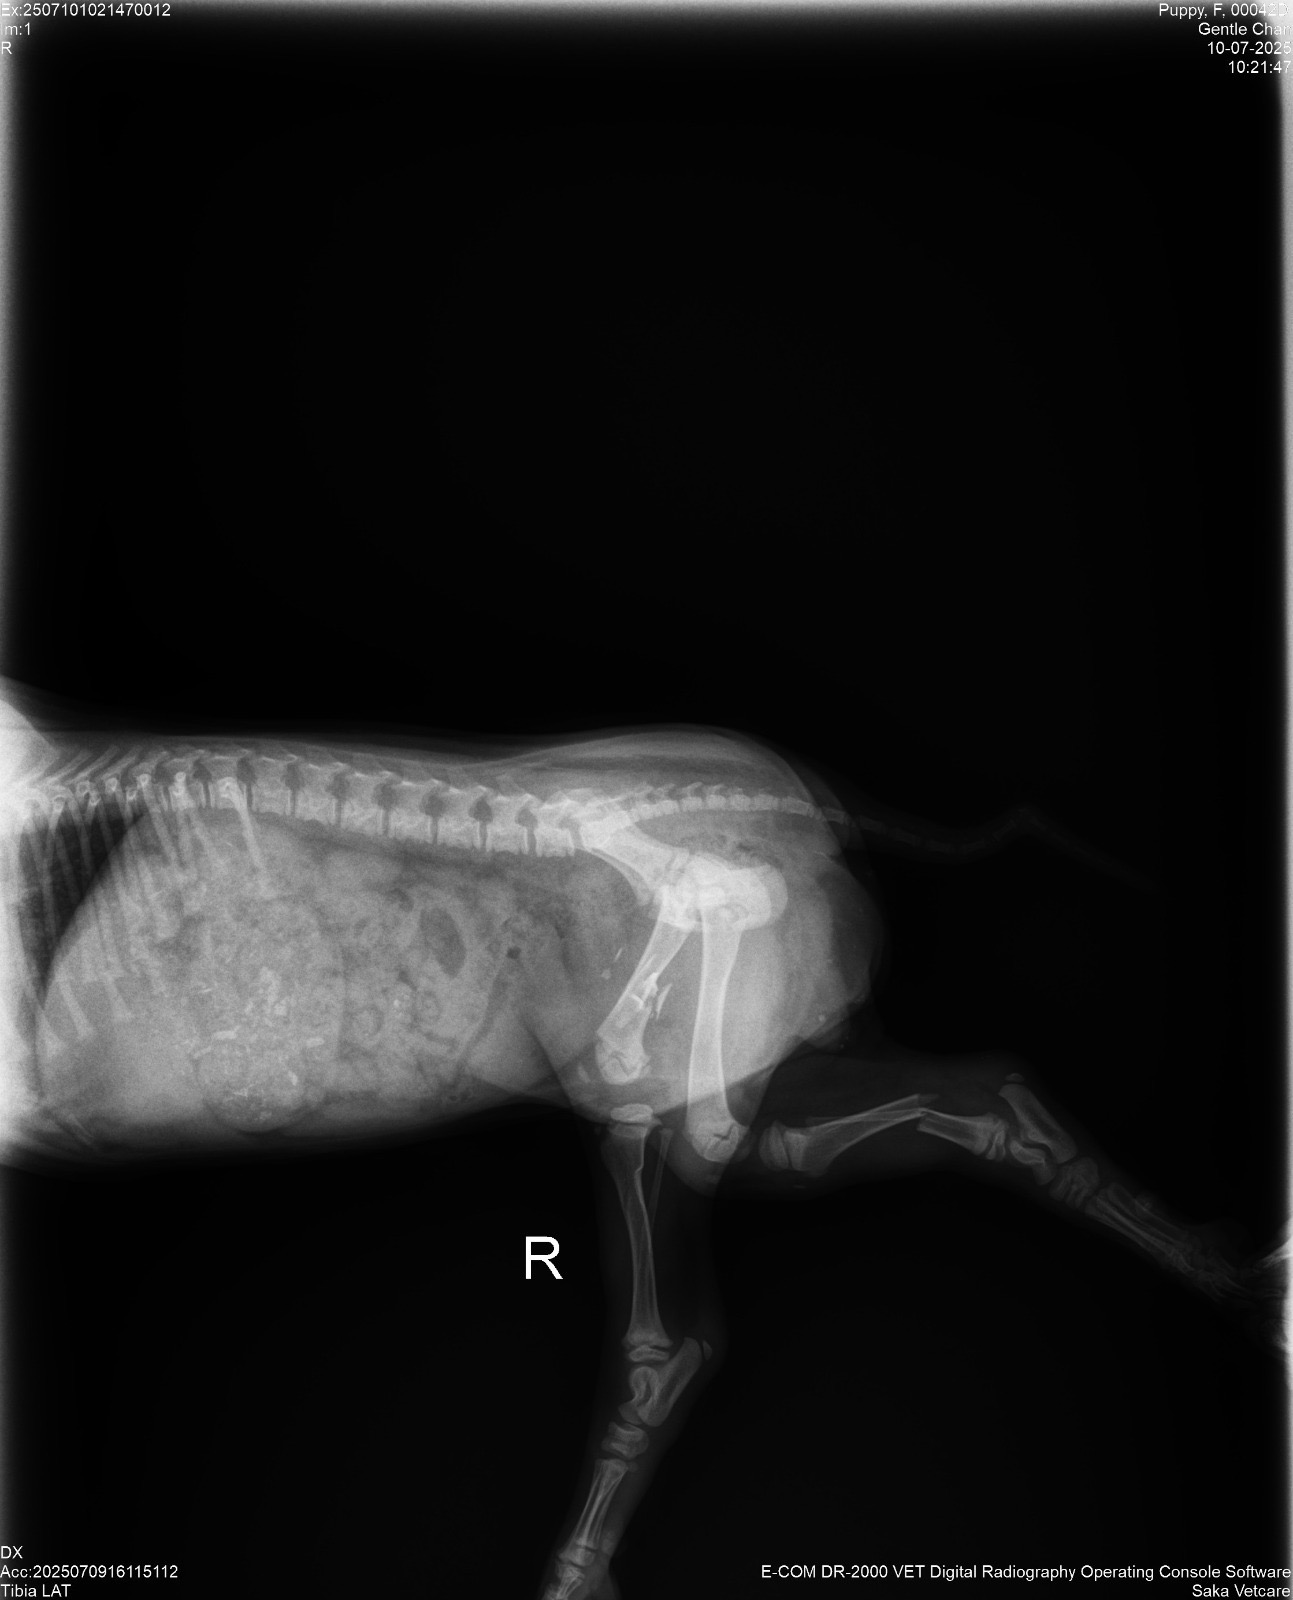

Kinta is a 6-week old purebred Kintamani puppy indigenous to Bali. I found her in poor shape outside of a hostel and brought her to a sanctuary that referred us to a clinic. After a consultation, some x-rays, casts, and medicine, we found that she had 3 breaks along her hind legs. With surgery, she has very good chances at making a full recovery. Without, she will likely be permanently disabled in both back legs.